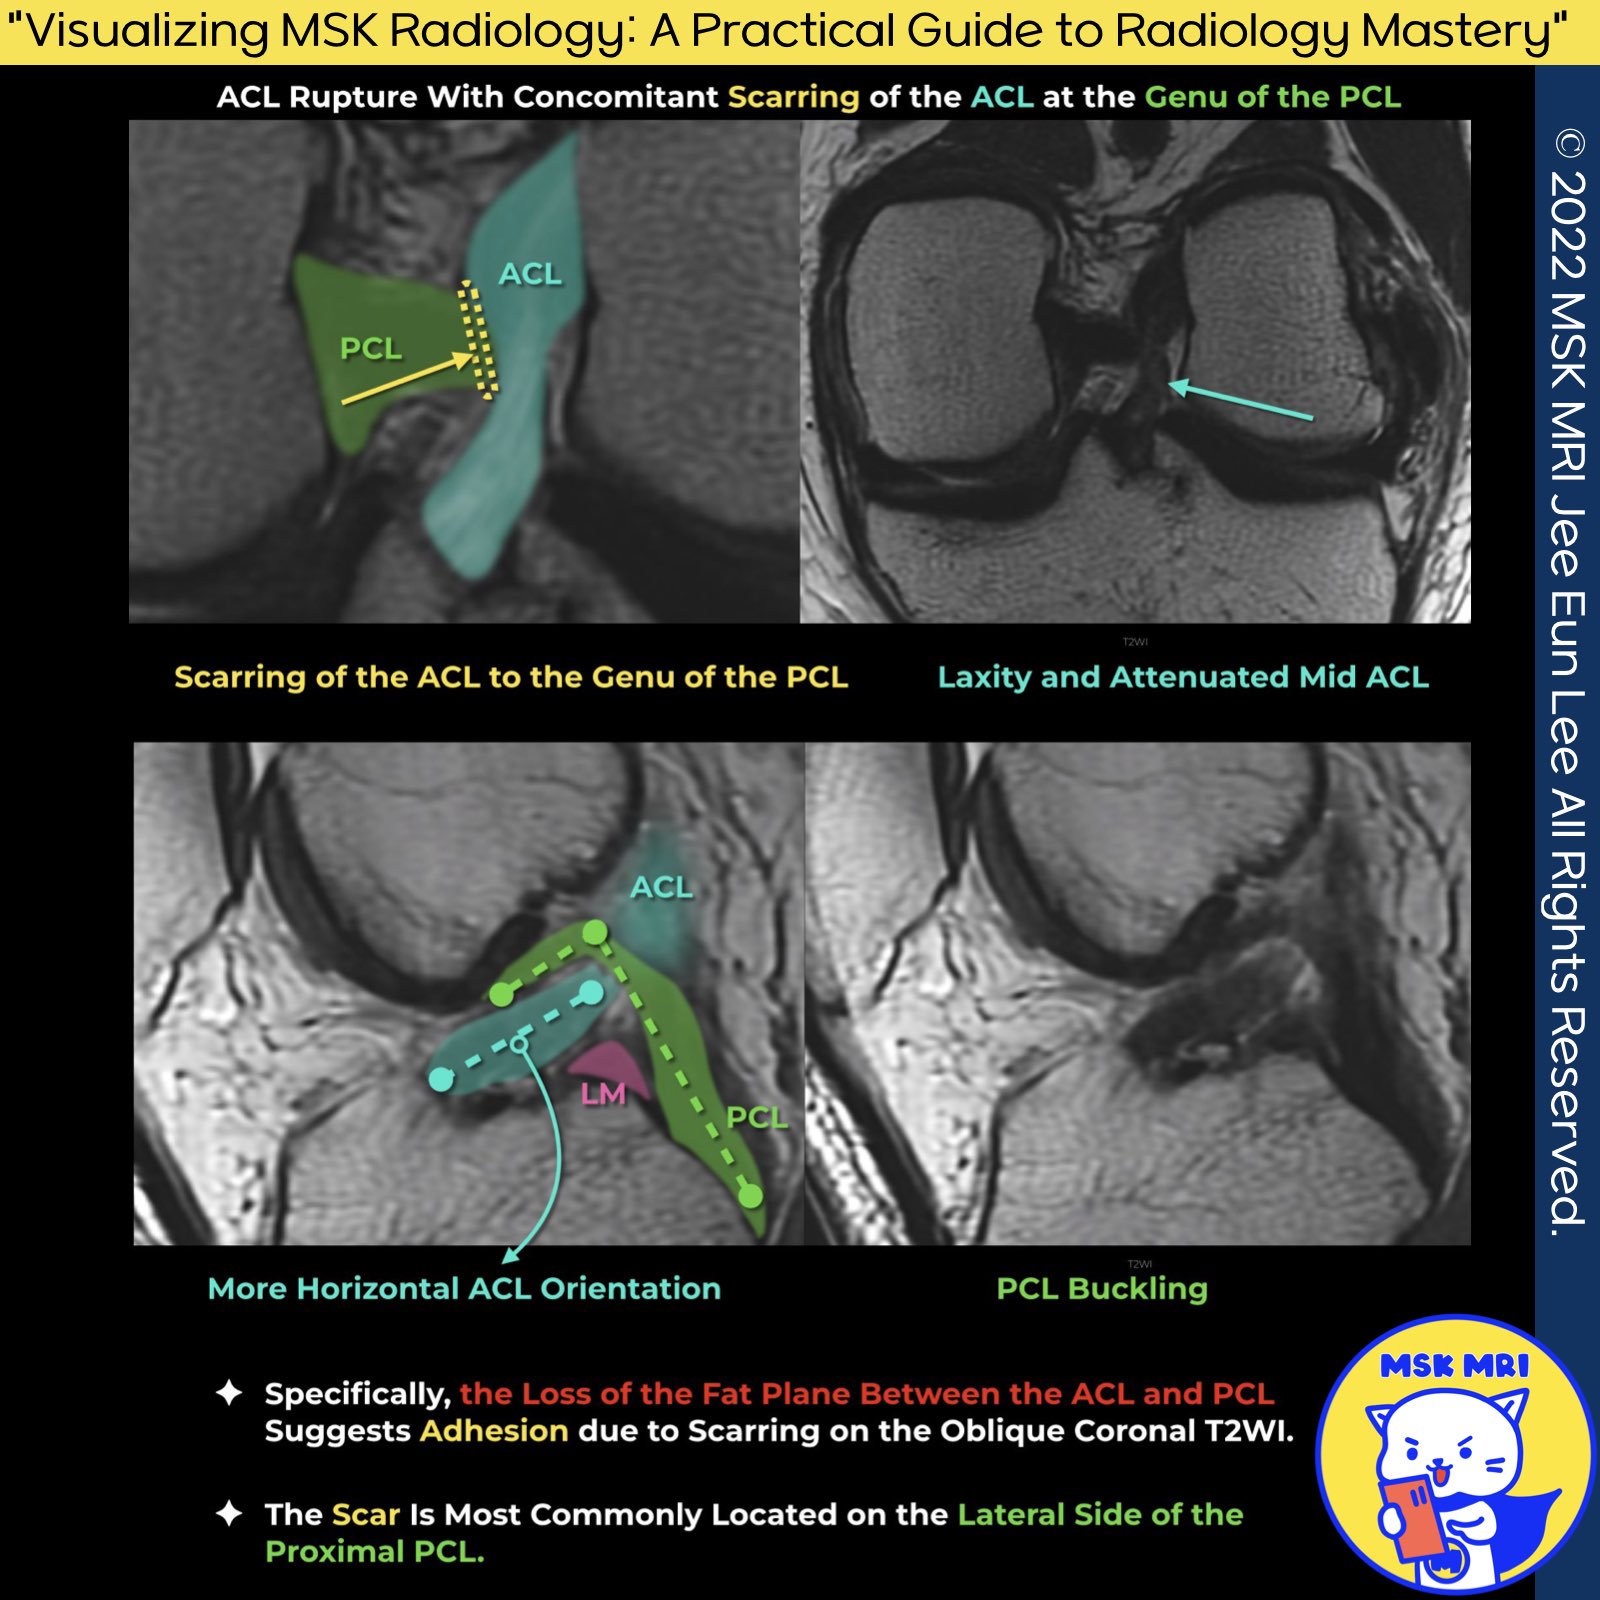

✅ ACL Scarring:

- The scar tissue from the ACL most frequently attaches to the lateral side of the proximal PCL and the intercondylar notch.

- It is less common for the scar to attach back to the ACL's original attachment point.

- Among these patterns, scarring that reconnects the ACL to its original attachment point is rare but results in the most significant improvement, leading to reduced laxity (looseness) during clinical examinations.

- Even if the ACL forms a continuous structure through scarring, the healed ligament is usually functionally weaker than before the injury.